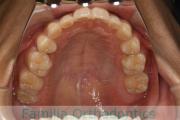

上の前歯の並びが気になるのできれいにしたい、ということで来院されました。マウスピース型矯正装置のひとつ、インビザライン/InvisalignR(薬機法および医薬品副作用被害救済制度の対象外)を用いて治療しました。

非抜歯で2年弱、20回程度の通院で治療が完了しました。

マウスピース矯正は、患者さんの協力に治療結果が左右されるところはリスクと言えるかもしれません。